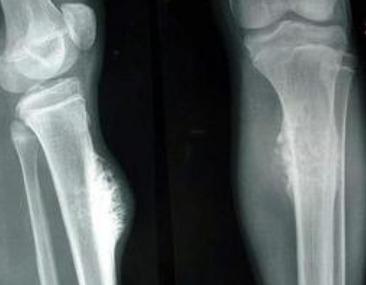

骨癌是一种恶性程度很高的癌症,治疗起来难度极大。为了对抗病魔,小李开始了漫长的治疗历程。他先后接受了化疗、放疗等多种治疗手段,承受了常人难以想象的痛苦。